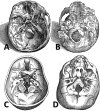

For a long time, because of its location at the skull base level, the sphenoid bone was rather mysterious as it was too difficult for anatomists to reach and to elucidate its true configuration. The configuration of the sphenoid bone led to confusion regarding its sutures with the other skull bones, its shape, its detailed anatomy, and the vascular and nervous structures that cross it. This article takes the reader on a journey through time and space, charting the evolution of anatomists' comprehension of sphenoid bone morphology from antiquity to its conception as a bone structure in the eighteenth century, and ranging from ancient Greece to modern Italy and France. The journey illustrates that many anatomists have attempted to name and to best describe the structural elements of this polymorphous bone.